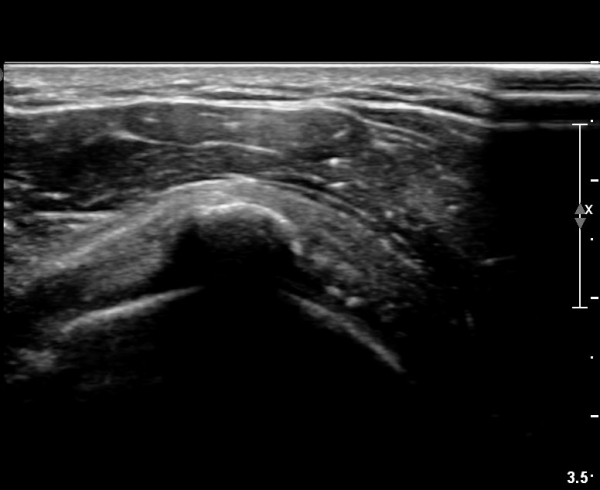

±Ø»ó°Ç Ⱦ´Ü¸é°Ë»ç¿¡¼­µµ ±Ø»ê°Ç³» ¼®È¸È­ µ¢¾î¸®°¡ °üÂûµÈ´Ù(»çÁø 2).